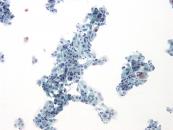

第35回日本臨床細胞学会九州連合会学会(宮崎)スライドカンファレンス症例1

種別:泌尿器

出題:長崎大学大学院医歯薬学総合研究科 病理学 林 洋子 先生

| 年齢 | 60歳代 | 性別 | 男性 |

| 採取部位 | 尿 | 採取方法 | 自然尿 |

既 往 歴:高血圧、高尿酸血症、PSA高値(9.17ng/ml)

現 病 歴:夜間頻尿にて受診。MRI検査にて、膀胱内腔へ突出する腫瘍が見られた。前立腺癌の尿道浸潤もしくは膀胱腫瘍が疑われた。

| 正解 | 4.膀胱原発腺癌 |

▼選択肢及び投票結果

| 1.尿細管上皮 | 10件 | (10.3%) | |

| 2.低異型度尿路上皮癌 | 4件 | (4.1%) | |

| 3.高異型度尿路上皮癌 | 4件 | (4.1%) | |

| 4.膀胱原発腺癌 | 20件 | (20.6%) | |

| 5.前立腺癌 | 59件 | (60.8%) | |

| 投票総数 | 97件 | (100%) |